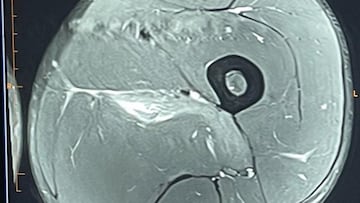

El serbio publica la imagen de una ecografía en la que se muestra la lesión muscular que le obligó a retirarse del Open de Australia.

El de Belgrado ha querido zanjar todo tipo de debate este sábado, cuando ha publicado en su cuenta de X la imagen de una ecografía en la que se aprecia una lesión muscular acompañada de un demoledor mensaje. “Pensé en dejar esto aquí para todos los “expertos” en lesiones deportivas”, afirmó Djokovic, que compartió una fotografía en la que se aprecia que la prueba médica se ha realizado este mismo 25 de enero a las 12:00 de Australia. Por si hubiese alguna duda, también se puede ver que la imagen pertenece al serbio.